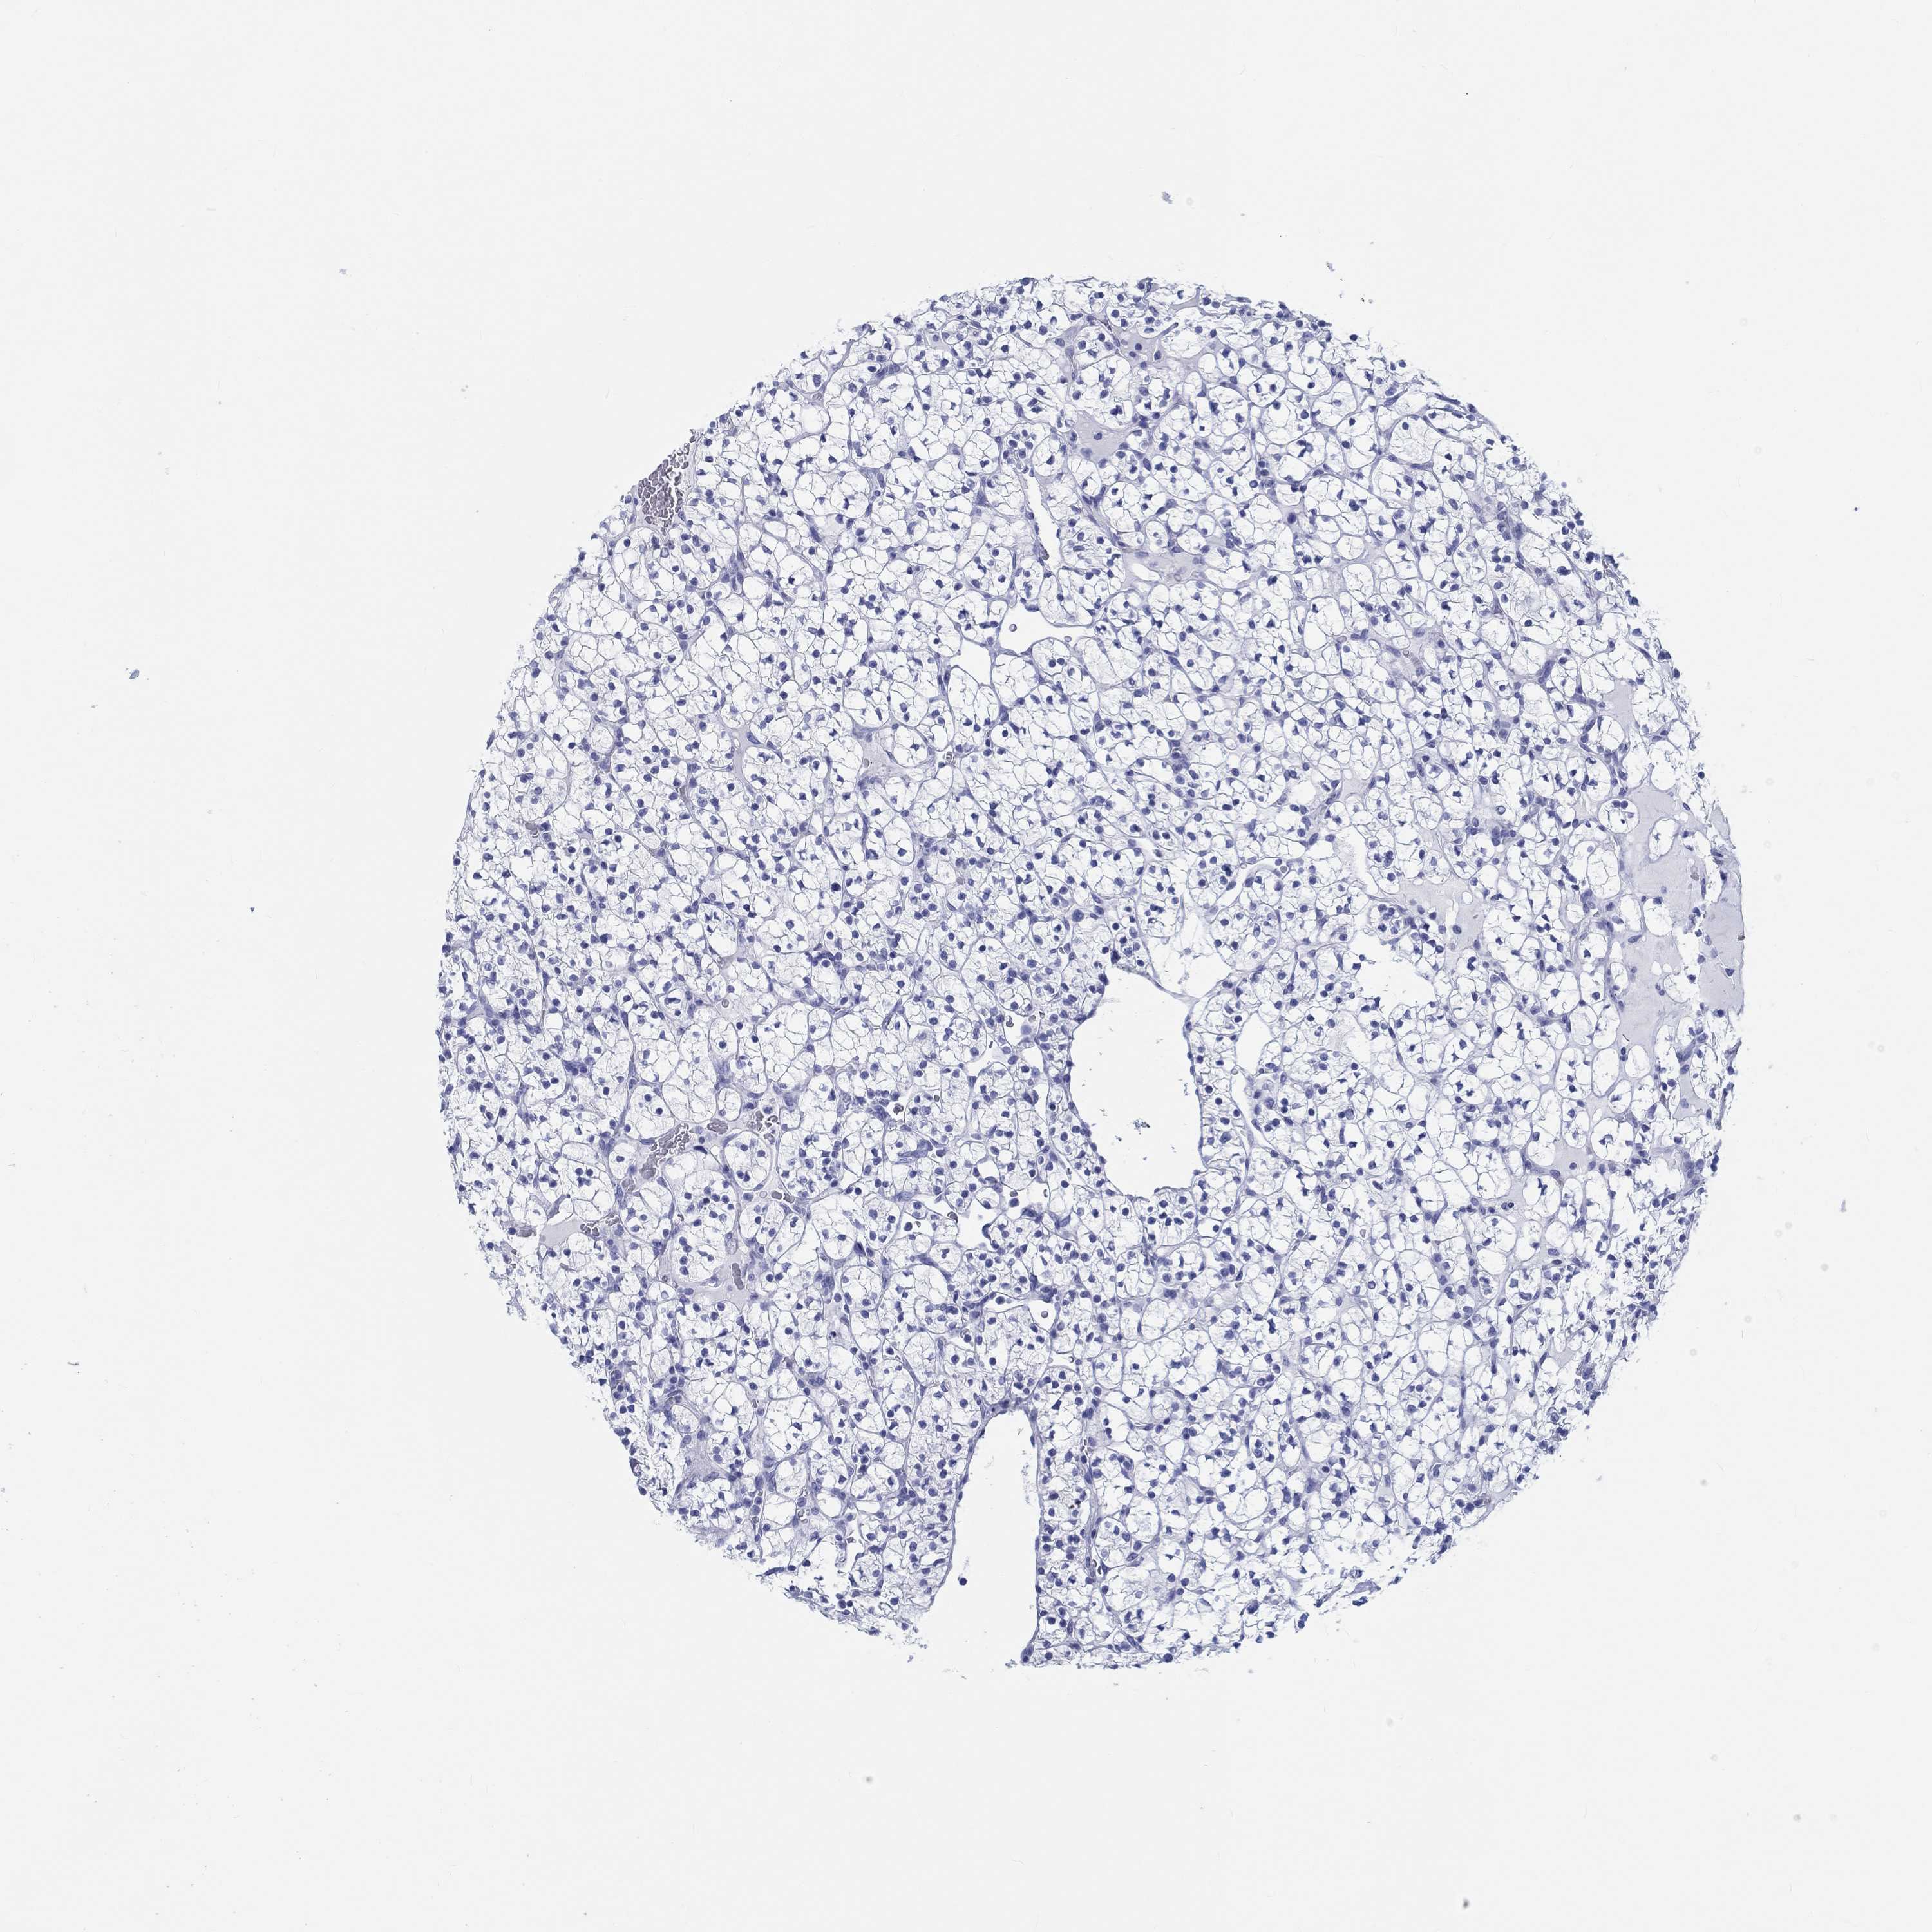

CANCER RENAL CANCER Show tissue menu

KICH TCGA KIRC TCGA KIRC VALIDATION KIRP TCGA PROTEIN RCC CPTAC PROTEIN EXPRESSION